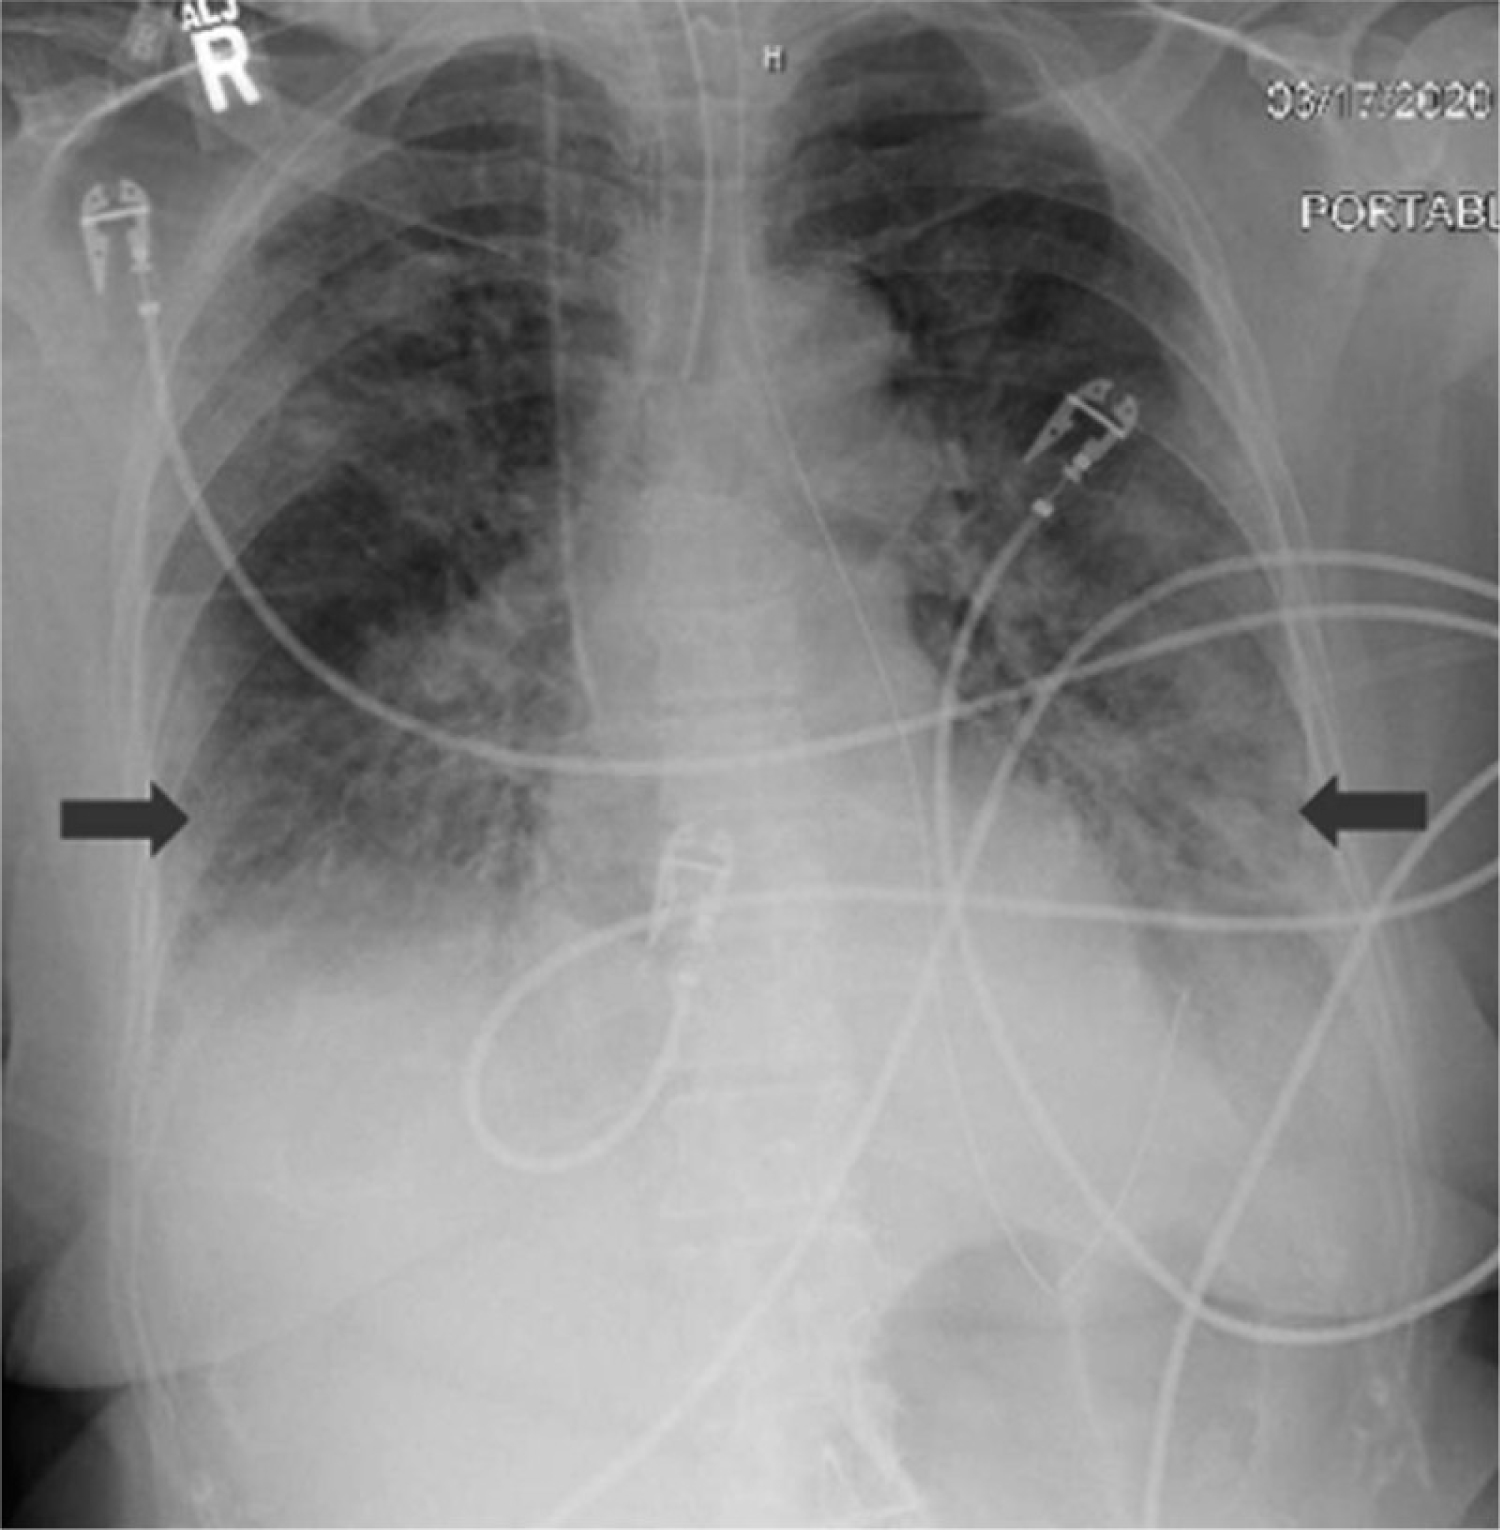

On June 14, he developed progressively worsening hypoxemic respiratory failure. The patient was managed by intermittent prone positioning, fluid restriction, and mechanical ventilation through the tracheostomy. Laboratory studies revealed rising serum inflammatory markers (Table 1). Repeated CT scan showed large area of ground-glass opacity with irregular density in the subpleural regions of both lungs, with 'crazy-paving sign, predominantly in the lower lobes, multiple patchy consolidations were apparent in both lungs, with air bronchus-charging sign and thickening of the pulmonary interstitium surrounding the lesions (Figure 1).

Figure 1: Chest CT scan on 12.06.2020 shows large areas of ground-glass opacity with irregular density in the subpleural regions of both lungs, with 'crazy-paving sign', predominantly in the lower lobes, multiple patchy consolidations were apparent in both lungs, with air bronchus-charging sign and thickening of the pulmonary interstitium surrounding the lesions. View Figure 1